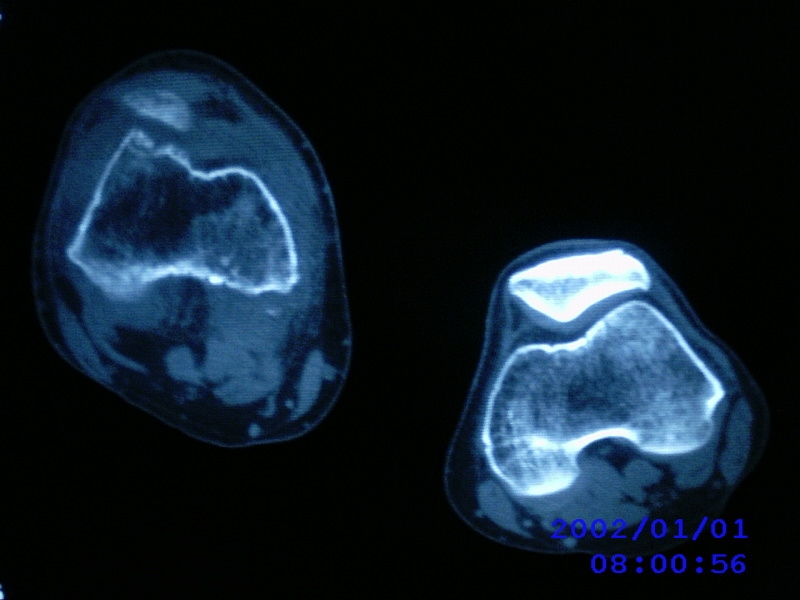

患者,男性,57岁,右侧膝关节疼痛伴肿脹10余年,加重一个月。

关节积液,关节间隙变窄,边缘骨破坏。考虑膝关节tb

关节积液,关节间隙变窄,骨质疏松,多发骨破坏,边缘轻度硬化,近端胫腓骨髓腔软组织充填,患者病史较长,支持考虑结核

有皮质的破坏~有死骨存在

多发骨破坏,骨质疏松,关节积液。考虑右膝关节结核。